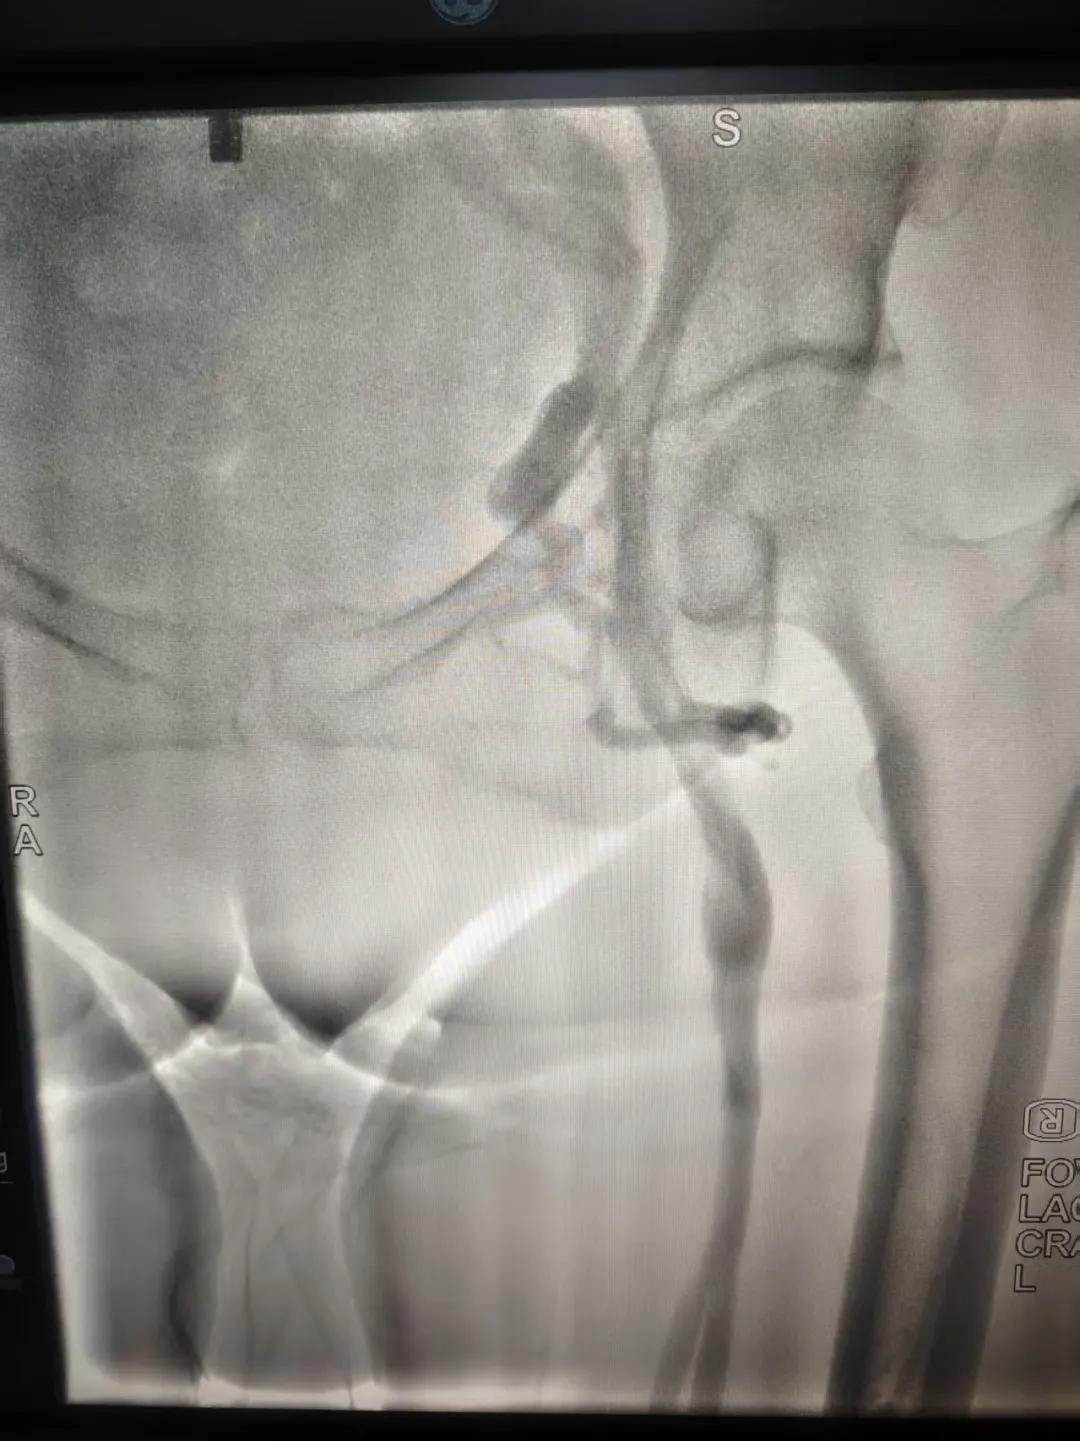

該患者,中年女性,左下肢反復(fù)腫脹、疼痛多年就醫(yī),未明病因。門(mén)診就診,經(jīng)血管外科副主任周創(chuàng)業(yè)評(píng)估病情后,為該患者門(mén)診行下肢靜脈造影,造影結(jié)果示:左髂靜脈周?chē)鷤?cè)枝形成,左髂靜脈壓迫綜合癥。明確診斷后將擇期介入手術(shù)治療。

下肢靜脈造影是診斷下肢靜脈病變(如深靜脈血栓、靜脈曲張、靜脈功能不全等)的“金標(biāo)準(zhǔn)”。靜脈造影可直觀顯示受壓部位、狹窄程度及側(cè)支循環(huán)形成情況,明確診斷與定位,指導(dǎo)治療決策,以及介入治療規(guī)劃,血栓評(píng)估,在復(fù)雜病例或介入治療中造影具有優(yōu)勢(shì)。